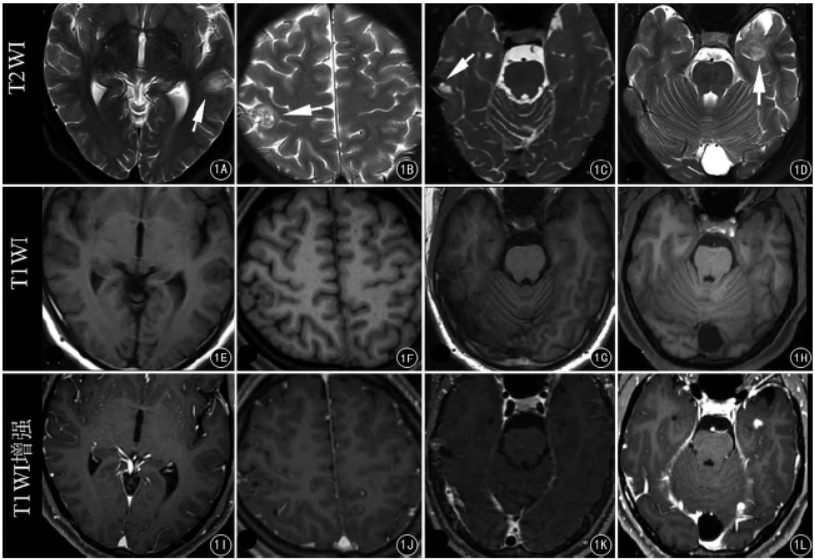

白质低信号(DWM)如何助力医生区分 NKH、MOG 脑炎与硬膜下血肿?